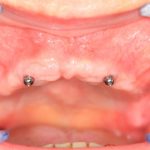

80-летняя бабушка жалуется на то, что у неё съемный протез выпадает, ей перед подругами по лавочке стыдно. И она ожидает, что мы придумаем какую-нибудь штуку, которая поможет её протезу держаться на челюсти и не выпадать.

Скажите, каким будет оптимальное решение в её случае? 2 импланта, шариковые абатменты или локаторы:

Просто фиксируем существующий протез к имплантам — и всё! Бабушка счастлива!